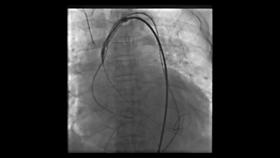

支架瓣膜输送中

于爷爷家人商量后接受了这一方案。医生为他麻醉后,心脏大血管外科副主任李伟栋主任医师从他大腿根部穿刺,将一根粗细不到6毫米的导管携带人工瓣膜及装置,从血管一直送到心脏瓣膜处,缓慢旋转导管逐渐释放瓣膜,通过精细调控,植入的人工瓣膜如花瓣一样在于爷爷心脏上完美绽放,手术成功!